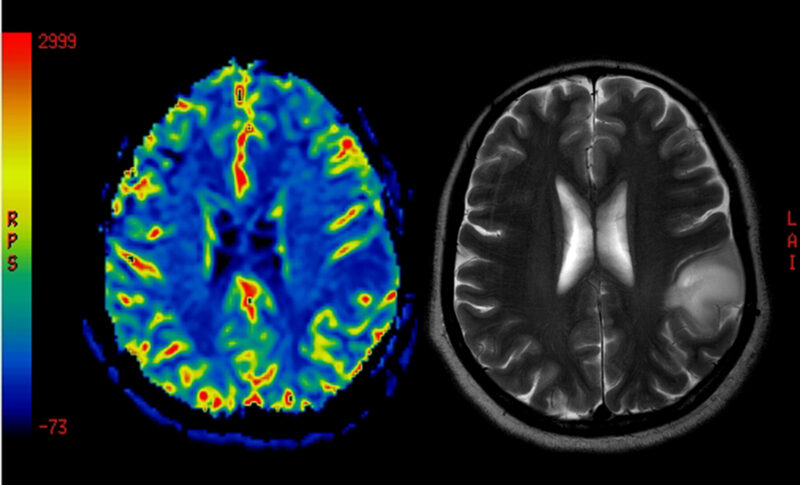

Treatment with the experimental nasal spray therapy foralumab reduced microglial activity in people with nonactive secondary progressive multiple sclerosis (SPMS), according to new data from an expanded access program. Microglia, the brain’s resident immune cells, are believed to contribute to the chronic inflammatory processes that drive gradual disease progression in the absence of relapses. These […]